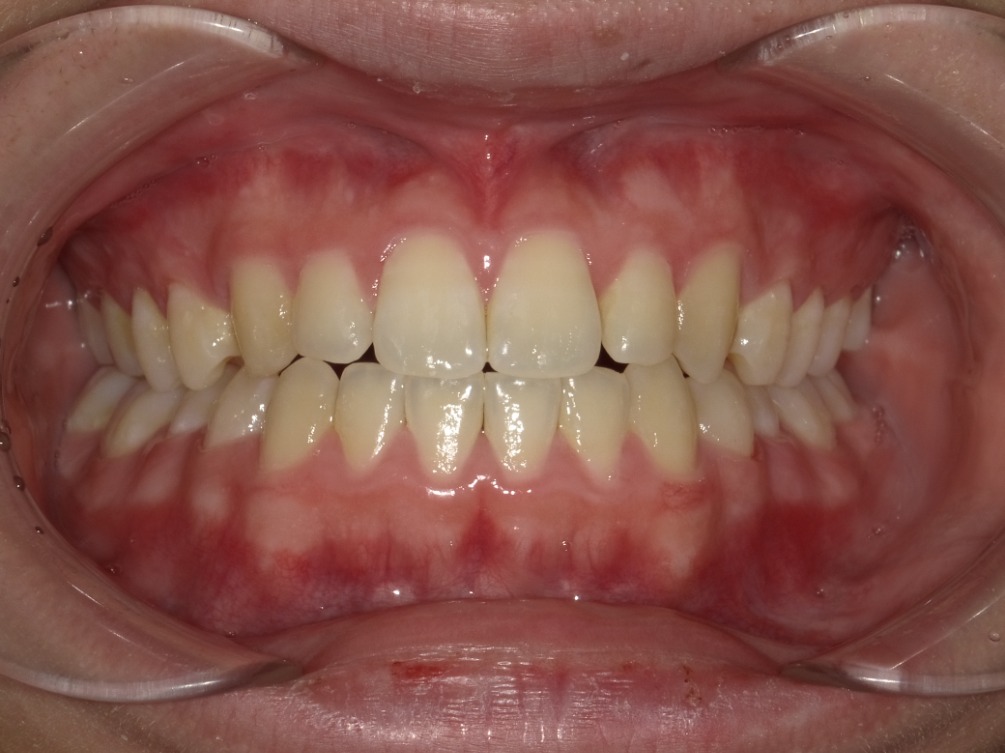

正面

| 治療内容 | インビザライン 全顎 |

| 治療詳細 | 反対咬合や叢生を整えるために、歯の表面にアタッチメント(白い突起)をつけ、IPR(歯と歯の間を削る)を行いました。 また、顎間ゴムと呼ばれる上顎と下顎に渡って引っ掛けるゴムの補助装置も用いて治療を行いました。 |

| 患者情報 | 10代 男性 デンタルモニタリング使用 |

| 主訴 | 下顎が前に出ている(受け口) 歯のがたつき |